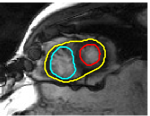

V-D Multiple Region Segmentation: Full Heart Segmentation

We now demonstrate our approach in performing challenging full heart segmentation: segmentation of the ventricles and epicardium all in one shot. Both the RV and epicardium are especially challenging as the contrast of the RV and background is subtle in comparison to the LV, and the myocardium wall near parts of the RV is very thin. We are not aware of another interactive method that is able to segment all structures, and so we compare to Medviso even though the method is not specifically tailored to the myocardium, but the method is generic and is able to propagate a segmentation. Further, Medviso does not segment multiple regions all at once and thus we perform separate segmentation of the LV, RV and epicardium. Since ground truth is not available for the outer wall of the myocardium in any standard dataset that we aware of, we show visual comparison.

Figure 10 shows the slice-wise results of our method and Medviso on a full 3D cardiac MRI sequence for a full cardiac cycle. Results indicate that our method is more accurate in capturing the shape of the ventricles and epicardium, and our method is especially more promising on the RV and epicardium. Figure 11 shows visualization of the results in 3D, and that our method more accurately resembles the structure of the heart.